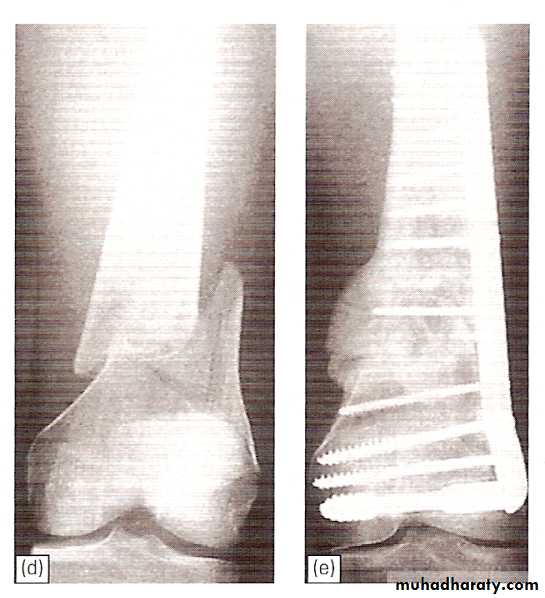

Supracondylar fractures of femur

In young adults after high energy injury.

In elderly osteoporotic after trivial injury.

Intercondylar extension may occur.

Supracondylar fracture with intercondylar extension

Supracondylar fracture femur

Treatment

Slightly displaced #s- skeletal traction through proximal tibia.If closed reduction fails- ORIF.

Locked intramedullary nail is the fixation of choice.